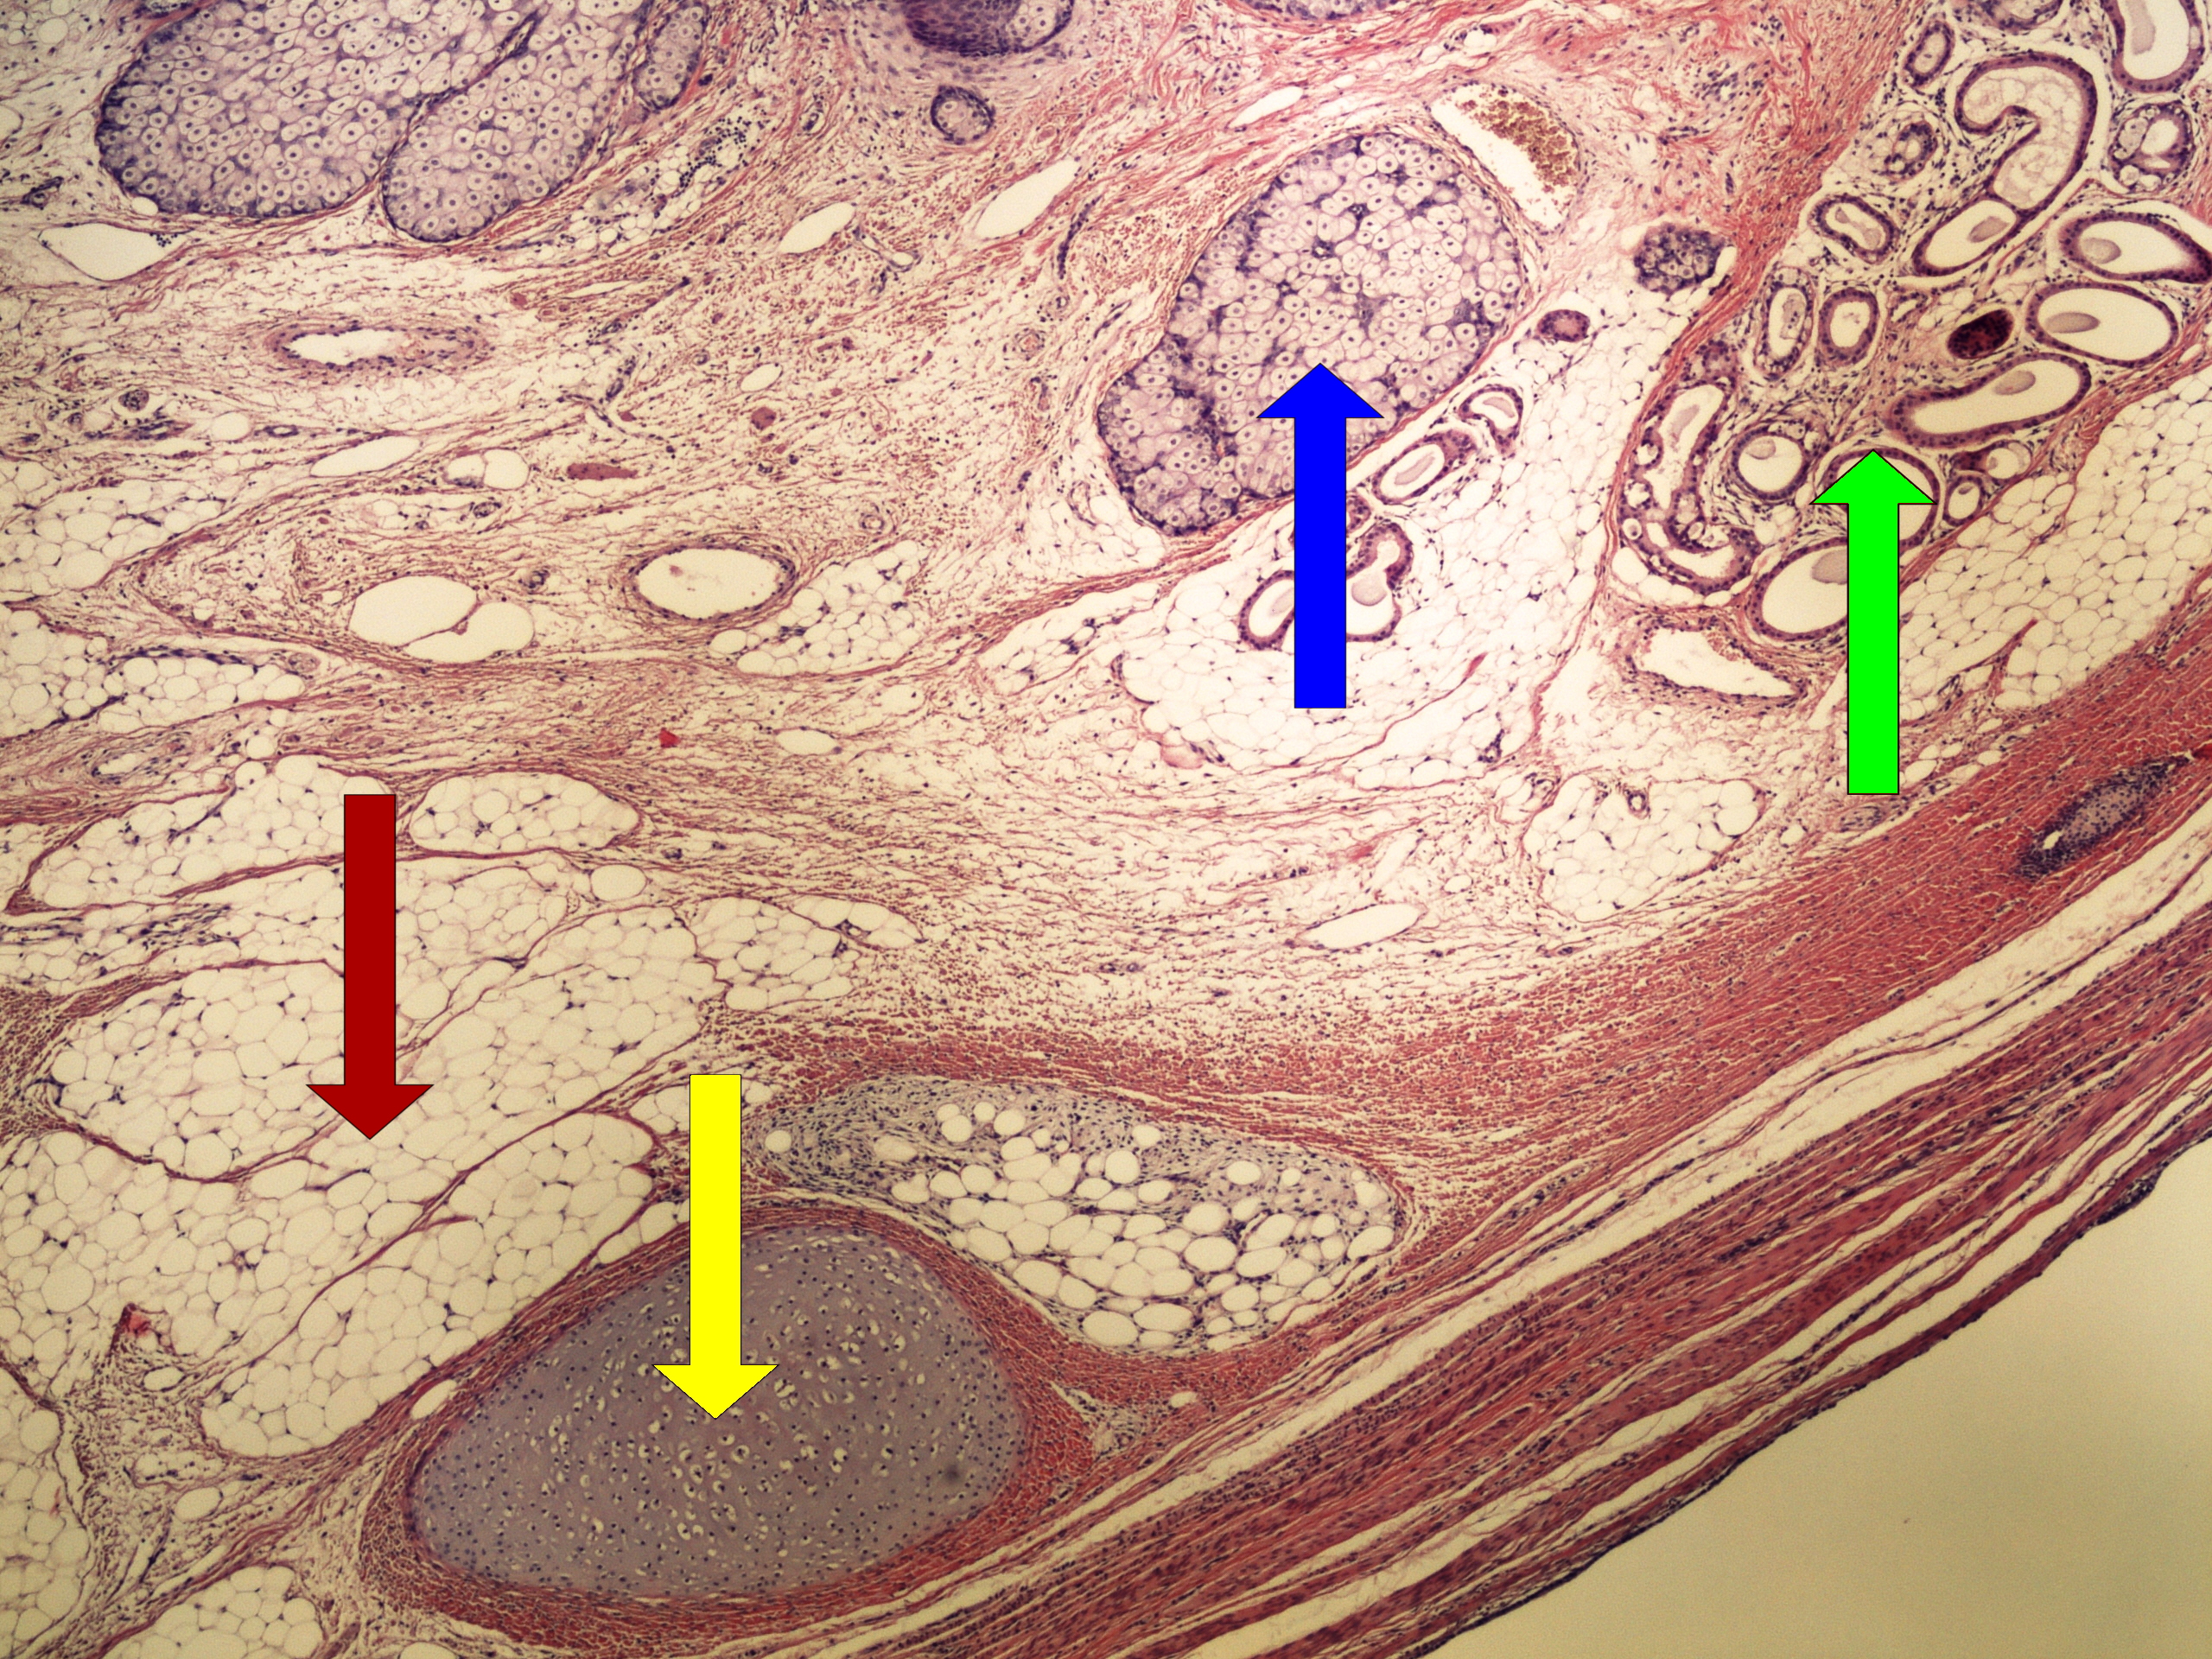

Патологическая анатомия рака яичников - фото презентация